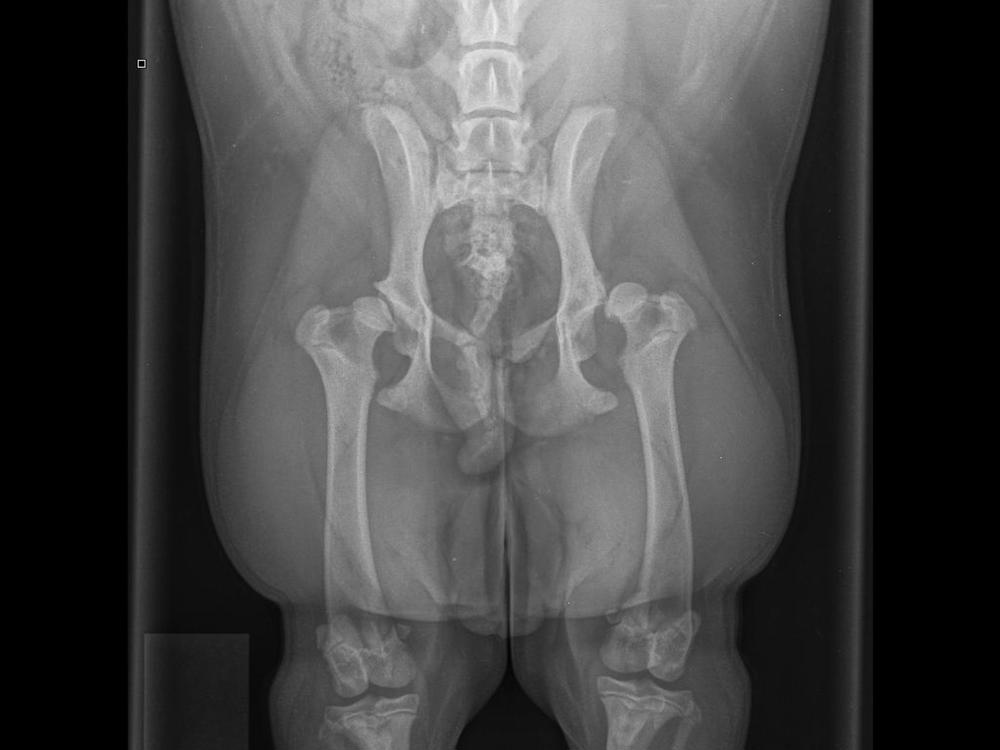

In Feb 2025 after we took Pepper to our vet for a limp, she was diagnosed with severe hip dysplasia, a dislocated left hip and a luxating patella.

Peppers medical bills are mounting up quicker than we can blink. To date we have had to switch her onto vet prescribed food, purchase special bedding, supplements and added gates to doorways in our home so she can’t access stairs. She has had x-rays, multiple vet visits, medications and received the first of her surgeries on the 20th of March which was the FHO procedure on her left hip. To date we have spent $2333.71 on vet bills alone. This doesn’t include the unpaid time off work I had to take to look after her during recovery.

Pepper now has MPL surgery booked with Massey on the 27th of May. This surgery will be to fix her patella - the quote for this is $3,500 - $4,500. As we live in South Taranaki this is going to add travel costs to and from her appointments.